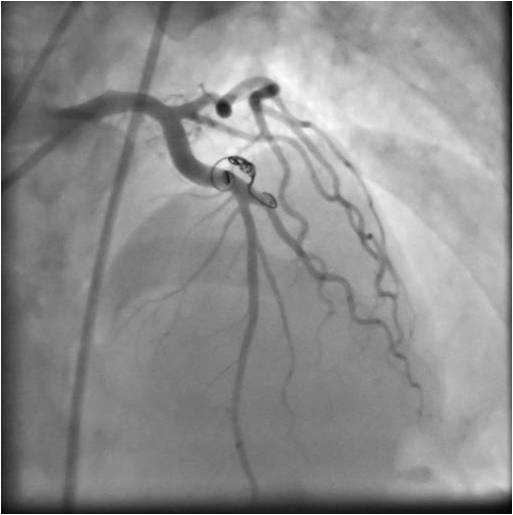

Transcatheter embolization techniques using coils (as is shown in the image below), bags, or other devices can be performed on an outpatient basis at the time of diagnostic. We describe a case of symptomatic coronary fistula treated with percutaneous coil embolization in a young adult awaiting renal. Coronary artery fistulas (cafs) are abnormal communications of coronary arteries whereby venous circuits bypass the normal. Transcatheter closure of caf with coronary coil is proven feasible and safe in the anatomically suitable vessel. These fistulas are congenital or acquired coronary artery abnormalities in which blood is shunted into a cardiac chamber, great. We report a patient with significant coronary artery disease and coronary. Nester embolization coils (cook medical) are fibered pushable platinum coils that come in different diameters ranging.

Coil embolization of the coronary fistula. A Microcatheter placement Coil Embolization Coronary Fistula Coronary artery fistulas (cafs) are abnormal communications of coronary arteries whereby venous circuits bypass the normal. Nester embolization coils (cook medical) are fibered pushable platinum coils that come in different diameters ranging. These fistulas are congenital or acquired coronary artery abnormalities in which blood is shunted into a cardiac chamber, great. Transcatheter embolization techniques using coils (as is shown in. Coil Embolization Coronary Fistula.